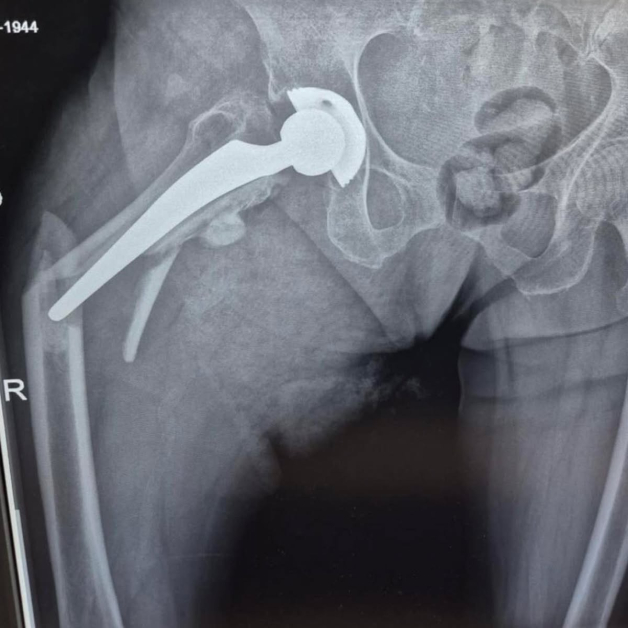

Животът на 80-годишна жена беше избавен след незабавна и сполучлива интервенция в Университетската многопрофилна болница за интензивно лекуване Каспела в Пловдив. Пациентката е с изкуствена тазобедрена става, сложена преди 7 години, само че след рухване е получила съществено строшаване на бедрената кост тъкмо под импланта.

Екипът на болничното заведение, отпред с доктор Димитър Генов и с присъединяване на доктор Благойчо Постоловски, е направил интервенцията бързо и точно. Използвано е особено ревизионно стебло, серклаж и циментна фиксация, с цел да се обезпечи непоклатимост на крайника.